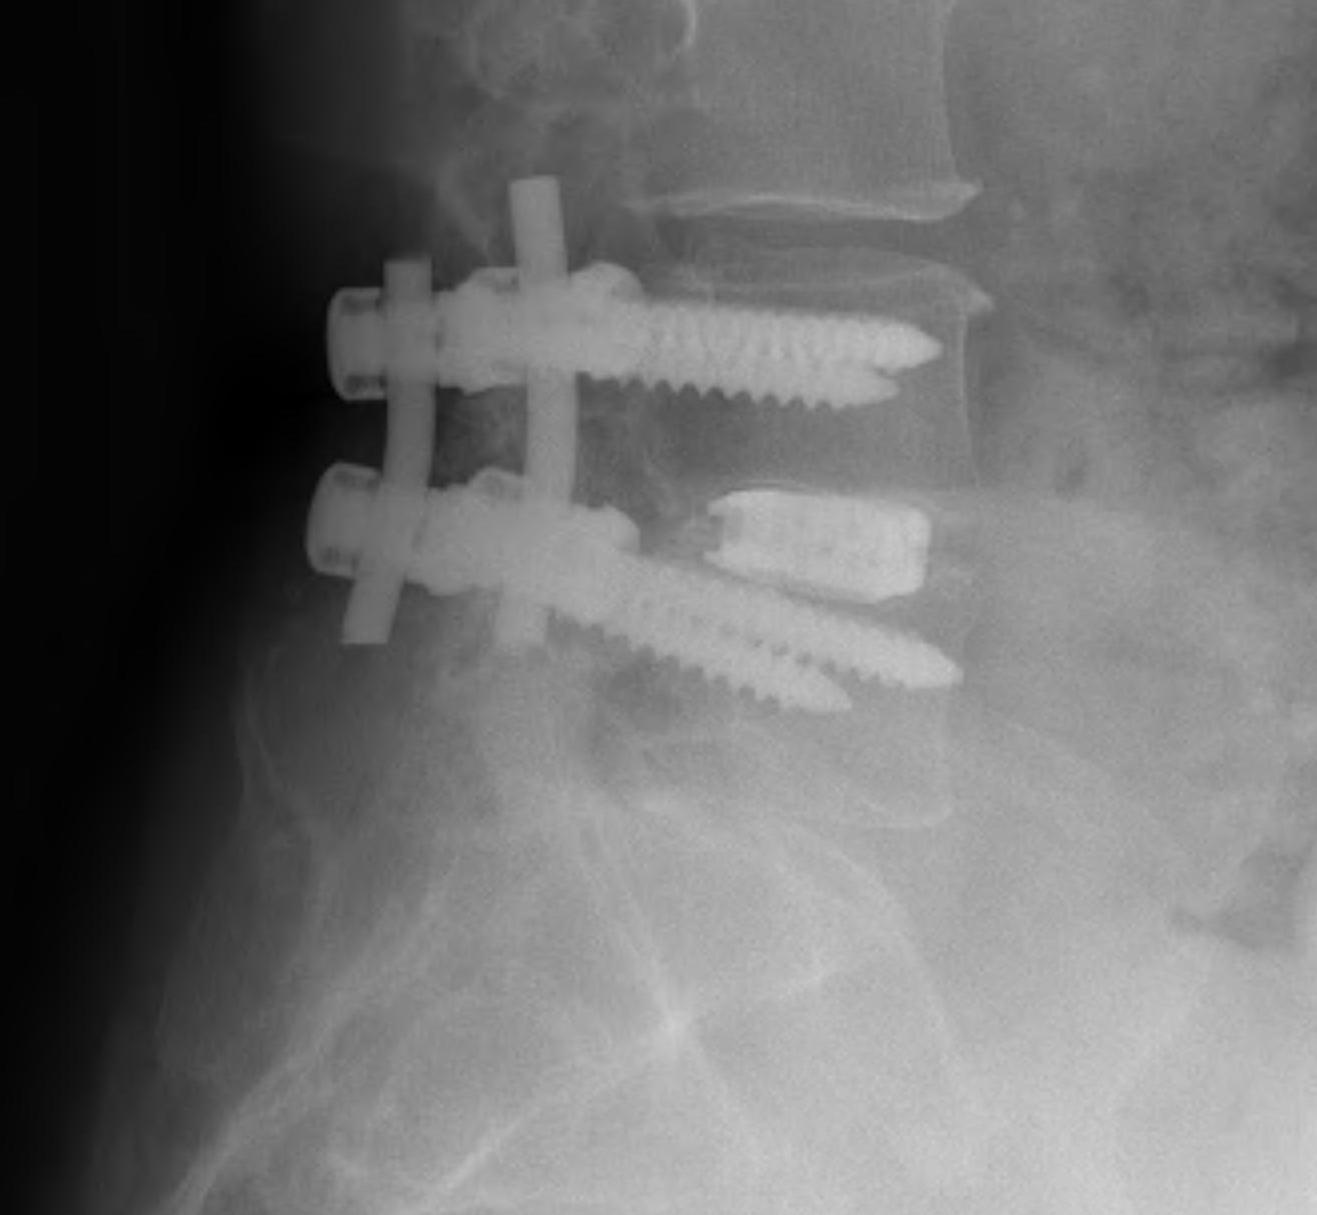

Technique

1. Wide laminotomy

- resection flavum, significant cranial lamina

- preserve if possible the posterior elements